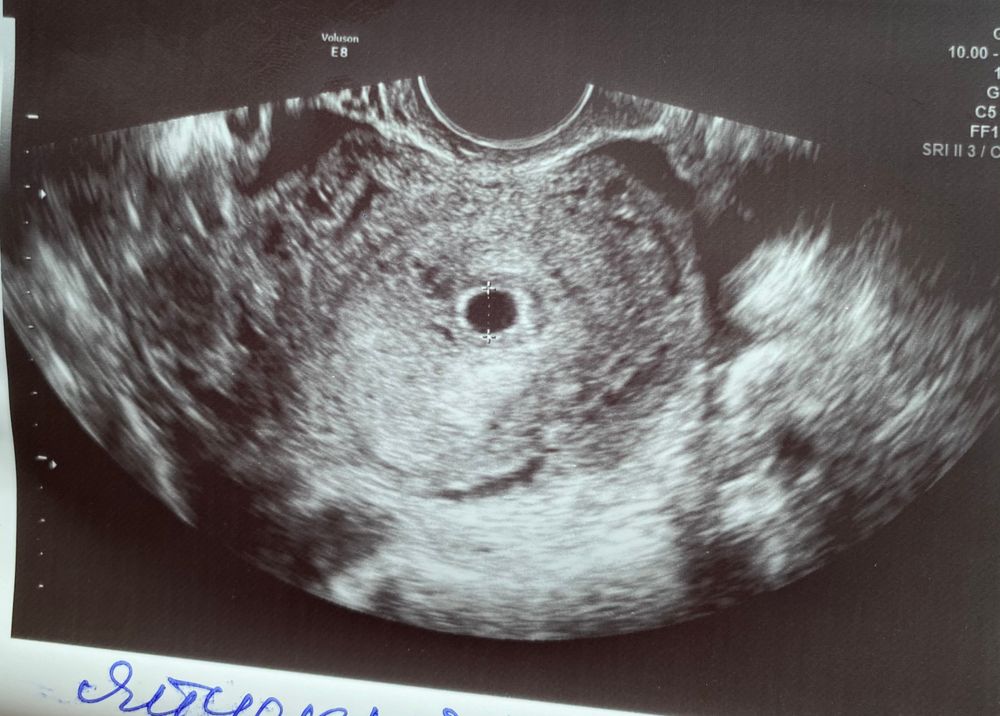

Татьяна , просто когда плодное яйцо пустое, там не будет никах точечек, даже маленьких. А у вас есть. Все хорошо.

ЖМ кажется вижу, ктр не вижу, но может разглядел, врачу виднее

Нина, я тоже вроде же вижу, но не ктр

Жм в правом нижнем углу есть,а эмбриона нет

Татьяна , странно, что тогда имел ввиду узист, вроде и пя должно быть больше на таком сроке (это если он перепутал) Ну может заработался человек, эмбриона и правда не видно🤷‍♀️

Какой размер ПЯ указали? Не вижу даже ЖМ 🤷🏼‍♀️

Не вижу и желточного мешка тоже